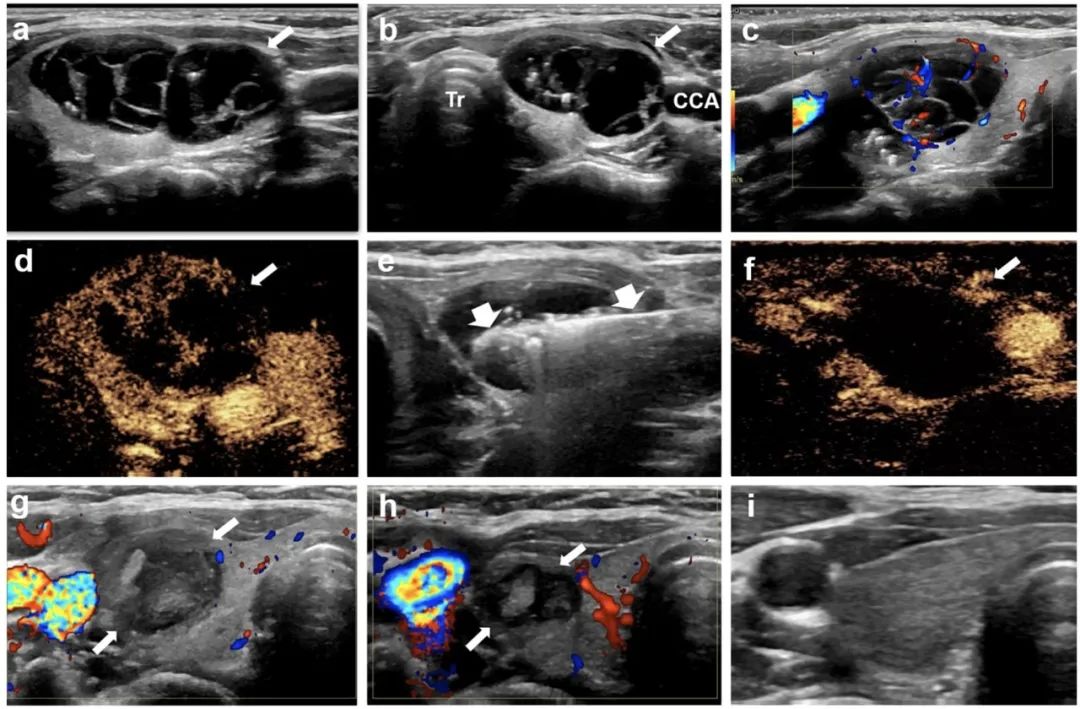

甲狀腺右葉囊性為主結(jié)節(jié),微波消融后3年,病灶完全消失

針對(duì)該問題,石文媛主任團(tuán)隊(duì)開創(chuàng)性地將微波消融技術(shù)應(yīng)用于兒童良性甲狀腺結(jié)節(jié)的治療。連續(xù)分析了2018年1月至2021年12月在北京兒童醫(yī)院接受經(jīng)皮微波消融治療的有癥狀良性甲狀腺結(jié)節(jié)患兒25名,共 34枚結(jié)節(jié)。所有患兒均隨訪半年以上(中位隨訪時(shí)間12個(gè)月,范圍6 - 48個(gè)月)。結(jié)果顯示:經(jīng)皮微波消融治療后,結(jié)節(jié)體積逐漸減?。ㄎ⒉ㄏ谇爸形惑w積5.86 mL,末次隨訪評(píng)估中位體積0.34 mL),末次隨訪評(píng)估體積縮小率達(dá)到85.03%,技術(shù)有效率達(dá)91.2%。結(jié)節(jié)相關(guān)壓迫癥狀、美容相關(guān)問題均得到顯著改善。術(shù)后一個(gè)月隨訪甲狀腺功能維持在正常范圍之內(nèi),提示微波消融在滅活甲狀腺結(jié)節(jié)的同時(shí)不影響正常甲狀腺功能。